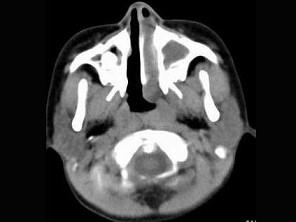

男,7岁,无意发现鼻腔肿物,无明显症状,CT如图所示,最可能诊断为 ( )

• A.鼻炎鼻息肉

答案: A